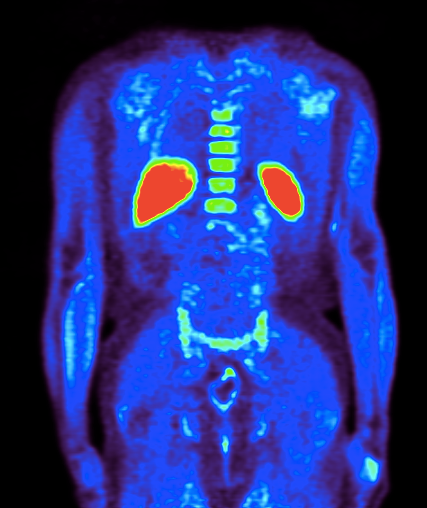

Prostate cancer detection using PETMaxim RossmannJul 1, 20141 min read Late imaging with [11C]acetate can improve detection of prostate cancer with PET: #PET #JNM #JournalofNuclearMedicine #11Cacetate